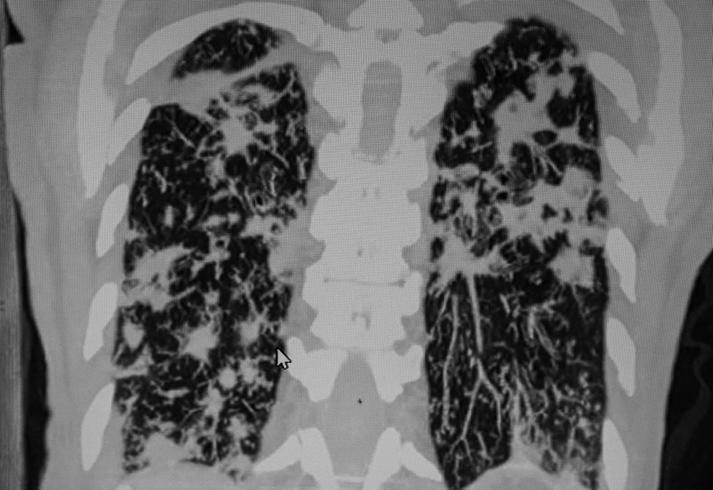

Lung Disease and COPD

AATD can lead to chronic obstructive pulmonary disease (COPD), a progressive lung disease that makes breathing a challenge. Neutrophil elastase, an enzyme, plays a dual role in lung health: it helps fight infections but can also damage healthy lung tissue if not regulated. Alpha-1 antitrypsin keeps neutrophil elastase in check, preventing lung damage after its infection-fighting role. COPD can cause symptoms like wheezing, coughing, and shortness of breath. AATD can also increase the risk of developing emphysema, a lung disease that damages the air sacs in the lungs due to unchecked neutrophil elastase activity. Patients with AATD may develop emphysema, a progressive condition characterized by damaged air sacs, resulting in severe respiratory issues and difficulty breathing. For those with severe lung disease, a lung transplant might be an option.